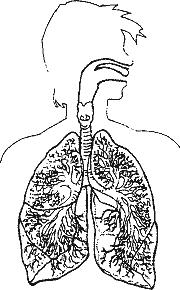

ДЫХАНИЕ

Гидромассажные ванны прежде всего улучшают глубокое дыхание и уменьшают его частоту. При глубоком дыхании лёгкие работают немного лучше. Это помогает избежать инфекций, что важно для тяжелобольных. При плохой вентиляции лёгких, в них скапливаются мокроты и пациенты чаще болеют воспалением лёгких.

Ингаляционные ванны

Концентрация эфирных масел в воздухе при купании в гидромассажной ванне в 30–50 раз больше, нежели при купании в простой ванне. Добавив в воду нужные препараты, можно успешно лечить астму, катар верхных дыхательных путей, грипп, воспаление лёгких, антракоз (скопление пыли в лёгких) и другие лёгочные заболевания.

При борьбе со всевозможными инфекциями, угрожающими тяжёлым больным рекомендуются ванны с более высокой температурой воды, так как в воздухе над поверхностью воды увеличивается концентрация эфирных масел.

Добавки: ёлочные и сосновые иглы, чабрец, экстракт эвкалипта и ромашка.